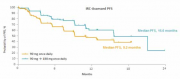

| 13:19, 16 בנובמבר 2017 | Alunbrig1.png (קובץ) |  |

73 קילו־בייטים | Motyk | 2 | |

| 12:15, 16 בנובמבר 2017 | Alunbrig3.png (קובץ) |  |

65 קילו־בייטים | Motyk | 1 | |

| 11:57, 16 בנובמבר 2017 | Alunbrig2.png (קובץ) |  |

1.63 מגה־בייטים | Motyk | 1 | |